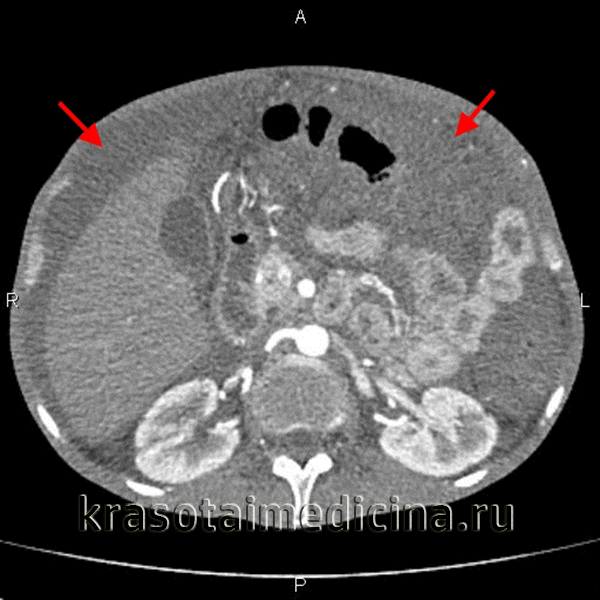

Добавлено: 22.03.2023, 03:53 Источник: Асцит – это вторичное состояние, характеризующееся накоплением экссудата или транссудата в свободной брюшной полости. Клинически проявляется увеличением объема живота, тяжестью, чувством распирания и болями в брюшной полости, одышкой. Диагностика асцита включает проведение УЗИ, КТ, УЗДГ, диагностической лапароскопии с исследованием асцитической жидкости. Для патогенетического лечения необходимо установить причину, вызвавшую скопление жидкости; к симптоматическим мероприятиям при асците относятся назначение мочегонных средств, пункционное удаление жидкости из брюшной полости. ![]() Общие сведения Асцит или брюшная водянка может сопровождать течение самого широкого круга заболеваний в гастроэнтерологии, гинекологии, онкологии, урологии, кардиологии, эндокринологии, ревматологии, лимфологии. Накопление перитонеальной жидкости при асците сопровождается повышением внутрибрюшного давления, оттеснением купола диафрагмы в грудную полость. При этом значительно ограничивается дыхательная экскурсия легких, нарушается сердечная деятельность, кровообращение и функционирование органов брюшной полости. Массивный асцит может сопровождаться значительной потерей белка и электролитными нарушениями. Таким образом, при асците может развиваться дыхательная и сердечная недостаточность, выраженные обменные нарушения, что ухудшает прогноз основного заболевания. Чаще всего асцит диагностируется у мужчин при циррозе печени. Патология может быть связана с повышением кровяного давления в системе воротной вены, воспалением брюшины, недостатком белка в организме. Так, причиной асцита становятся следующие заболевания и состояния: - перитонит; - мезетелиома брюшины; - полисерозит вследствие ревматизма, ревматоидного артрита, системной красной волчанки; - метастазы и прорастание в брюшину злокачественных опухолей из других органов; - цирроз печени, гепатоз, гепатит алкогольной этиологии; - тяжелые воспалительные патологии кишечника; - хроническая сердечная недостаточность; - непроходимость венозных сосудов вследствие их сужения или закупорки; - хронический гломерулонефрит почек; - заболевания крови; - панкреатит; - поражение матки и придатков; - голодание, строгая диета, вегетарианство. Также асцит обнаруживается в поздних стадиях гепатоцеллюлярного рака. Патогенез В норме серозный покров брюшной полости – брюшина продуцирует незначительное количество жидкости, необходимое для свободного движения петель кишечника и предупреждения склеивания органов. Этот экссудат всасывается обратно самой же брюшиной. При целом ряде заболеваний секреторная, резорбтивная и барьерная функции брюшины нарушаются, что приводит к возникновению асцита. Таким образом, в основе патогенеза асцита может лежать сложный комплекс воспалительных, гемодинамических, гидростатических, водно-электролитных, метаболических нарушений, вследствие чего происходит пропотевание интерстициальной жидкости и ее скопление в брюшной полости. Классификация асцита В зависимости от объема скопившейся жидкости выделяют следующие степени асцита: - легкая – водянка определяется только по результатам УЗИ; - средняя – присутствует равномерное симметричное умеренное увеличение живота; - тяжелая – характерно выраженное увеличение живота. Если транссудат стерилен, отсутствует гепаторенальный синдром, асцит имеет неосложненное течение. При присоединении инфекции и нарушении функций жизненно важных органов развивается осложненная форма заболевания. Также патологию классифицируют по ответу на медикаментозную терапию: заболевание поддается лечению; рефрактерный асцит, применение диуретиков неэффективно или невозможно из-за развивающихся осложнений. Симптомы асцита Часто первым признаком асцита для больного становится невозможность застегнуть брюки или ремень из-за увеличения обхвата талии. Если пациент контролирует вес, он может отметить его прибавку. Как на начальном этапе, так и при тяжелой степени водянки брюшной полости возможно появление следующих симптомов: - быстрая утомляемость; - тяжесть, ощущение распирания внутри живота; - боль, преимущественно с правой стороны; - тошнота, изжога, отрыжка; - повышенное газообразование в кишечнике; - затрудненное дыхание, одышка; - отечность рук, ног, посинение конечностей; - повышение общей температуры тела. При асците, связанном с патологией печени, увеличению живота могут сопутствовать или предшествовать пожелтение кожи, слизистых оболочек, потемнение мочи, обесцвечивание кала, появление синяков на теле, повышенной кровоточивости. Для туберкулеза характерно появление водянки вследствие поражения регионарных лимфоузлов и сдавления внутренних органов. Развитию такого осложнения обычно предшествуют повышенная утомляемость, чрезмерная потливость, преимущественно в ночные часы, потеря веса, продолжительный субфебрилитет 37–38°С, иногда слабые боли в животе. Пороки сердца и хроническая сердечная недостаточность из-за перераспределения крови также могут сопровождаться скоплением жидкости в брюшной полости. Симптомам асцита при этом зачастую предшествует продолжительное наблюдение у кардиолога. Таким больным важно обращать внимание на нарастающую слабость и одышку, ночной кашель, выраженные колебания показателей АД. Отеки присутствуют на нижних конечностях, усиливаются к вечеру или вовсе не проходят в течение дня. При почечной патологии, напротив, отекают лицо и верхняя половина тела. Проявления асцита при онкологии разнообразны, зависят от локализации и агрессивности опухоли. Неизменным остается лишь значительное увеличение объема живота. При большом объеме жидкости присутствует расширение подкожных вен на животе, выпячивание пупка. Диагностика В ходе осмотра гастроэнтеролога исключаются другие возможные причины увеличения объема живота – ожирение, киста яичника, беременность, опухоли брюшной полости и т. д. Для диагностики асцита и его причин проводится перкуссия и пальпация живота, УЗИ брюшной полости, УЗДГ венозных и лимфатических сосудов, МСКТ брюшной полости, сцинтиграфия печени, диагностическая лапароскопия, исследование асцитической жидкости. ![]() Перкуссия живота при асците характеризуется притуплением звука, смещением границы тупости при изменениях положения тела. Прикладывание ладони к боковой поверхности живота позволяет ощутить толчки (симптом флюктуации) при постукивании пальцами по противоположной стенке живота. Обзорная рентгенография брюшной полости позволяет идентифицировать асцит при объеме свободной жидкости более 0,5 л. Из лабораторный тестов при асците проводится исследование коагулограммы, биохимических проб печени, уровней IgA, IgM, IgG, общего анализа мочи. У пациентов с портальной гипертензией показано выполнение ЭГДС с целью обнаружения варикозно измененных вен пищевода или желудка. При рентгеноскопии грудной клетки может выявляться жидкость в плевральных полостях, высокое стояние дна диафрагмы, ограничение дыхательной экскурсии легких. В ходе УЗИ органов брюшной полости при асците изучаются размеры, состояние тканей печени и селезенки, исключаются опухолевые процессы и поражения брюшины. Допплерография позволяет оценить кровоток в сосудах портальной системы. Гепатосцинтиграфия проводится для определения поглотительно-экскреторной функции печени, ее размеров и структуры, оценки выраженности цирротических изменений. С целью оценки состояния спленопортального русла проводится селективная ангиография – портография (спленопортография). Всем пациентам с асцитом, выявленным впервые, выполняется диагностический лапароцентез для забора и исследования характера асцитической жидкости: определения плотности, клеточного состава, количества белка и бактериологического посева. При сложно дифференцируемых случаях асцита показано проведение диагностической лапароскопии или лапаротомии с прицельной биопсией брюшины. Лечение асцита Всем больным рекомендованы ограничение физической нагрузки и потребляемого питья, соблюдение постельного режима, щадящая бессолевая диета. Медикаментозная терапия асцита включает прием мочегонных препаратов. При повышенной потере белка возможно внутривенное введение раствора альбумина. Выраженная водянка, которая сопровождается сдавлением внутренних органов, в тяжелых случаях требует откачивания с помощью иглы скопившегося экссудата через прокол брюшной стенки. Данная процедура называется лапароцентезом, проводится только по показаниям из-за большого количества возможных осложнений. Прогноз при асците зависит от его выраженности и причины возникновения. Как правило, он существенно осложняет течение основного заболевания, поэтому сопровождается высокой летальностью. |